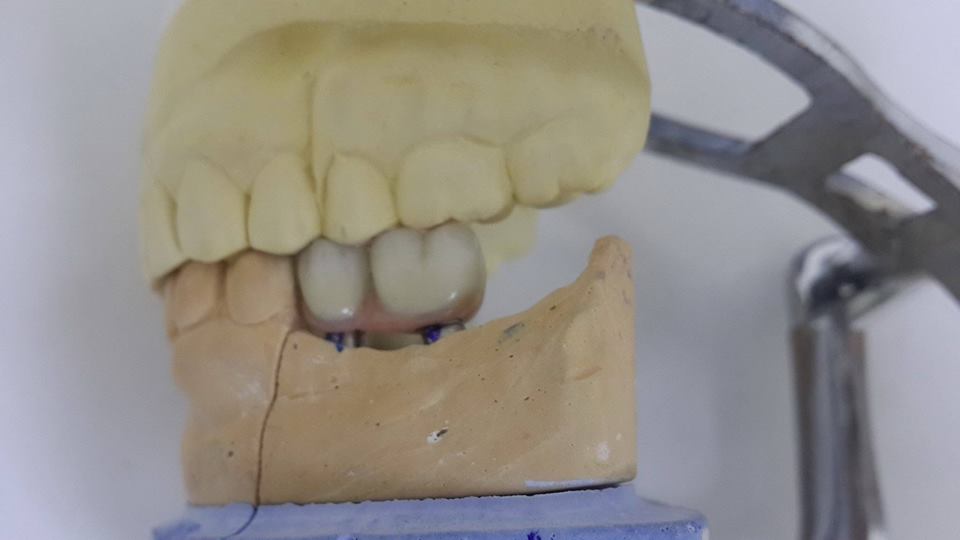

An example of complete rehabilitation of the oral cavity. Treatment included the removal of the old prosthesis, treatment of paradontitis, removal of a large cyst, implantation, clasp prosthesis.